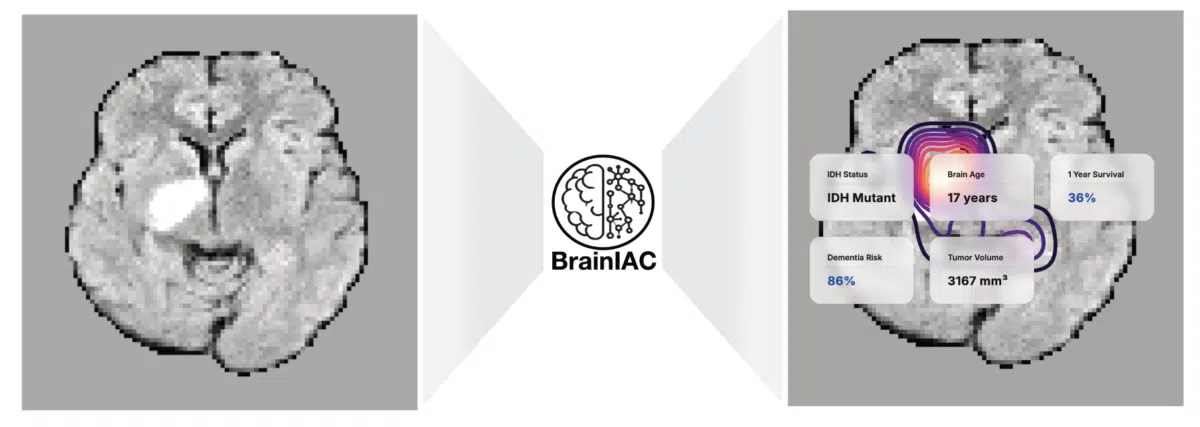

Ερευνητές από την Ιατρική Σχολή του Χάρβαρντ ανέπτυξαν το BrainIAC, ένα ενιαίο μοντέλο τεχνητής νοημοσύνης ικανό να αναλύει μαγνητικές τομογραφίες του εγκεφάλου, για μια σειρά παθήσεων- από την νόσο Αλτσχάιμερ έως τον καρκίνο. Αυτή η καινοτόμος προσέγγιση εξαλείφει την ανάγκη δημιουργίας ξεχωριστών αλγορίθμων για κάθε ασθένεια, προσφέροντας σημαντικά οφέλη όσον αφορά την αποτελεσματικότητα και την ακρίβεια. Θα μπορούσε επίσης να επιταχύνει την ανάπτυξη εργαλείων τεχνητής νοημοσύνης για σπάνιες ασθένειες που επηρεάζουν μικρούς πληθυσμούς ασθενών, όπου η συλλογή χιλιάδων επισημασμένων παραδειγμάτων δεν είναι εφικτή.

Στη συνέχεια, το δοκίμασαν σε επτά εντελώς διαφορετικές ιατρικές προκλήσεις: αναγνώριση τύπου μαγνητικής τομογραφίας, εκτίμηση της ηλικίας ενός ατόμου από τη δομή του εγκεφάλου του, πρόβλεψη των ποσοστών επιβίωσης ασθενών με καρκίνο, ανίχνευση σημαντικής γενετικής μετάλλαξης σε όγκους, έγκαιρη διάγνωση της άνοιας, εκτίμηση του χρόνου που έχει περάσει από το εγκεφαλικό επεισόδιο ενός ατόμου και χαρτογράφηση ορίων όγκων.

Το μοντέλο εκτέλεσε εργασίες που είναι δύσκολες ή αδύνατες για τους γιατρούς μόνο από την ανάλυση μαγνητικών τομογραφιών. Η πρόβλεψη γενετικής μετάλλαξης σε όγκους, που κανονικά απαιτεί χειρουργείο και γενετικές εξετάσεις, πέτυχε τιμή AUC 0,79- ένα εντυπωσιακό αποτέλεσμα για διάγνωση μόνο από μαγνητικές τομογραφίες.

Οι ερευνητές διαπίστωσαν ότι το μοντέλο επικεντρώθηκε σε συγκεκριμένες περιοχές του εγκεφάλου. Η χαρτογράφηση έδειξε ότι το BrainIAC επικεντρώθηκε στον ιππόκαμπο για την ανίχνευση άνοιας, σε ορισμένες περιοχές της λευκής ουσίας που αλλάζουν με την ηλικία και στον πυρήνα των όγκων για τις προβλέψεις καρκίνου. Οι χάρτες προσοχής ευθυγραμμίστηκαν με την γνωστή νευροανατομία, υποδηλώνοντας ότι το μοντέλο μάθαινε ιατρικά σημαντικά χαρακτηριστικά και όχι αυθαίρετα μοτίβα.